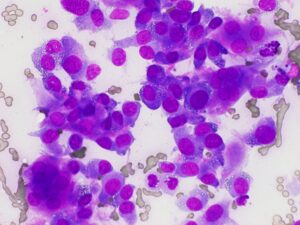

細い注射針を用いた細胞診を行いますが確定的な診断結果とならない場合があるので、太い骨髄生検針を使った病理組織検査を実施することがあります。